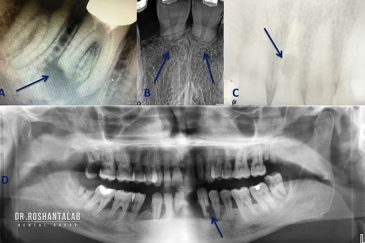

از عصب کشی و درمان ریشه دندان گرفته تا جراحی لثه و کشیدن دندان، تمامی مراحل توسط متخصص ترمیم دندان مدیریت میشود. ارائه باکیفیتترین خدمات ترمیم دندان برای سلامتی شماست.کاشت ایمپلنت فوری دندان